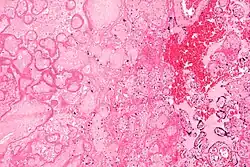

| Micrograph of a placental infarct. H&E stain. | |

A placental infarction results from the interruption of blood supply to a part of the placenta, causing its cells to die.

Small placental infarcts, especially at the edge of the placental disc, are considered to be normal at term. Large placental infarcts are associated with vascular abnormalities, e.g. hypertrophic decidual vasculopathy, as seen in hypertension.[1] Very large infarcts lead to placental insufficiency and may result in fetal death. Placental infarcts are generally detected after birth, although using ultrasound may be a way to notice infarcts prenatally. This method still needs more research and may not be completely effective in noticing infarcts. [2]

Maternal floor infarcts are not considered to be true placental infarcts, as they result from deposition of fibrin around the chorionic villi, i.e. perivillous fibrin deposition.